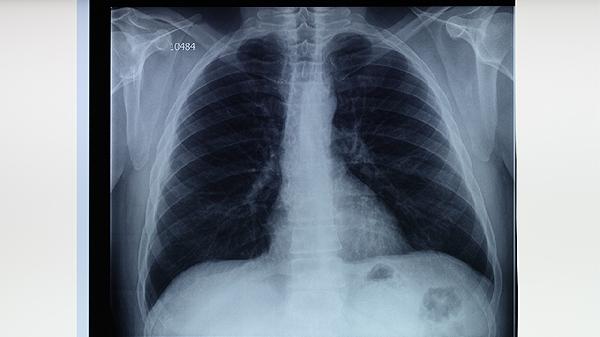

結(jié)核病密切接觸者、HIV感染者、糖尿病患者等高危人群應(yīng)定期進(jìn)行胸部X線或結(jié)核菌素試驗(yàn)檢查。出現(xiàn)咳嗽、低熱、盜汗等可疑癥狀超過(guò)2周時(shí)需及時(shí)就醫(yī)。醫(yī)務(wù)人員應(yīng)每年進(jìn)行職業(yè)健康檢查,早期發(fā)現(xiàn)潛伏結(jié)核感染。